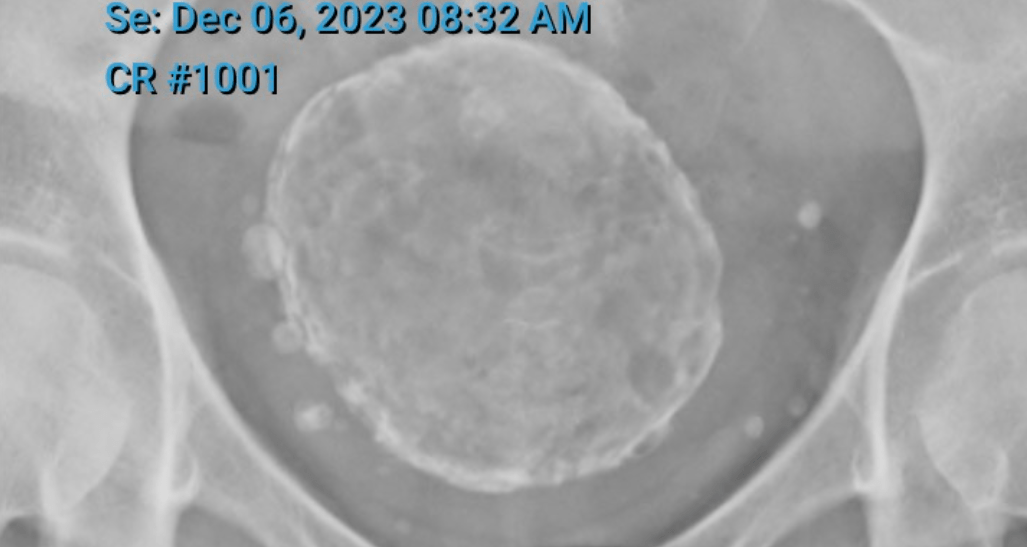

• Arrive at 7.15am for a 7.30am pelvic ultrasound to check how Freddie the Fibroid is going

I’d also forgotten that my gyno said I couldn’t have a muffler-through-tailpipe hysterectomy because Freddy was as wide as a full-term baby’s head.

I wish I could forget the three hours I spent in a specialist’s waiting room two years ago hoping he would say he could bag Freddie, blow him to bits and extract him that way. But no, apparently there’s no good reason to do that other than me feeling funny about having a fibroid the size of a 13-week foetus inside me.

Well, at least that’s how big he was last time they measured him. Will advise on his current measurements when I receive them. Bet you can’t wait!